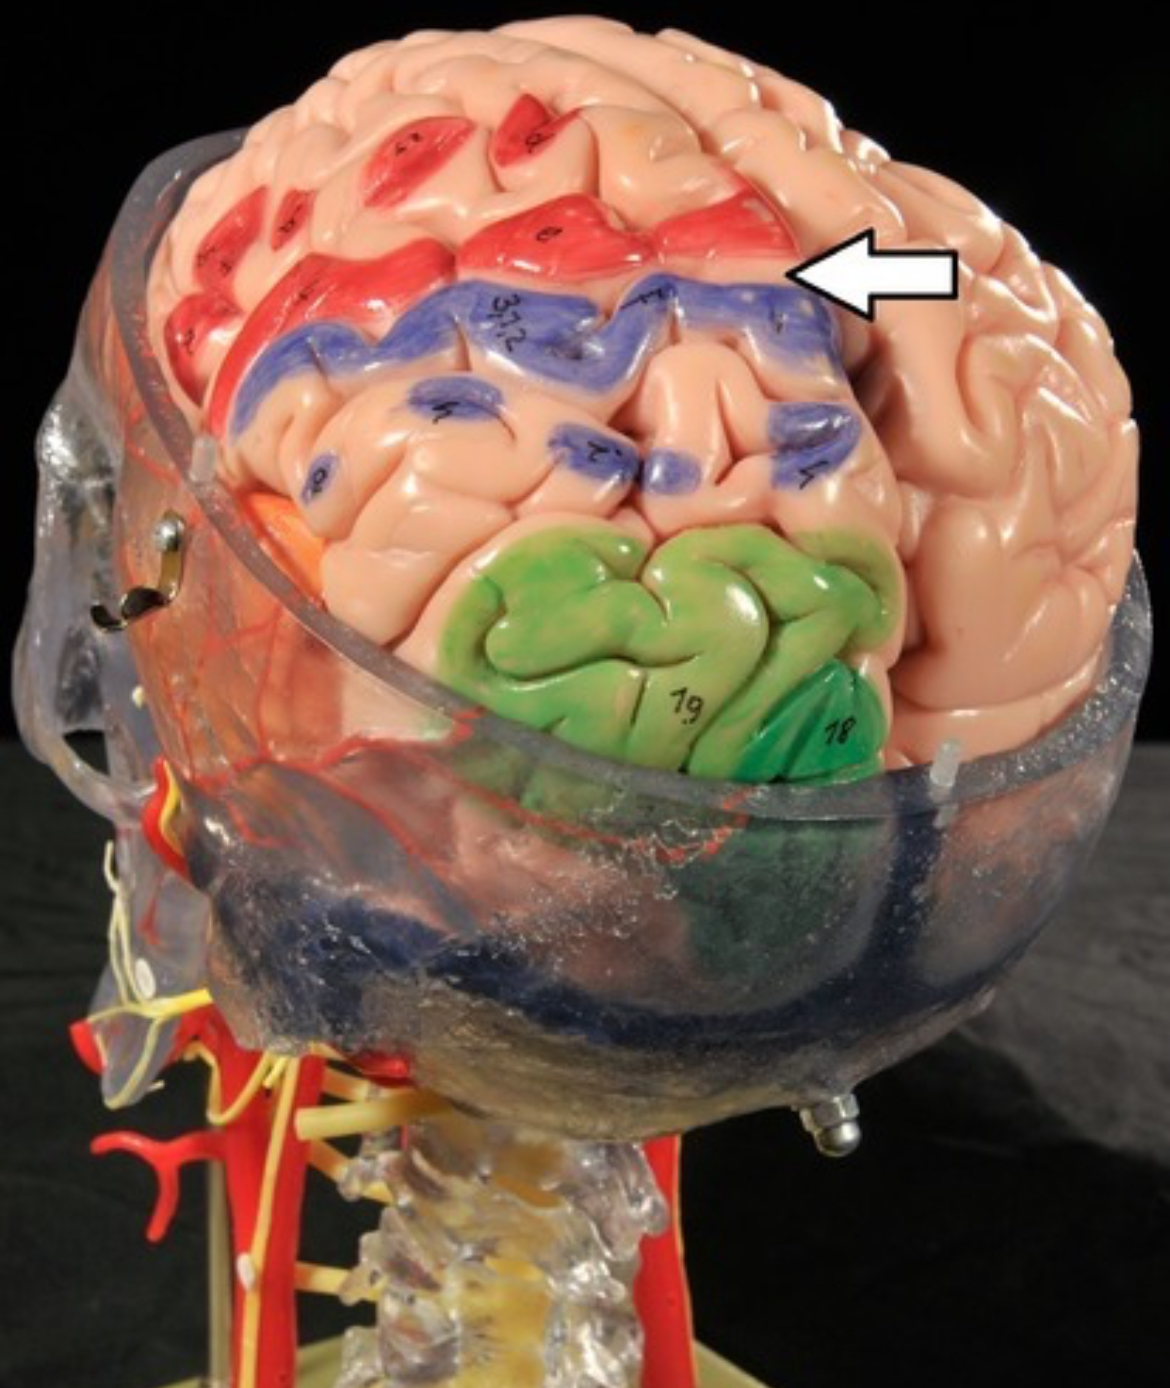

Precentral gyrus

Postcentral gyrus

Central sulcus